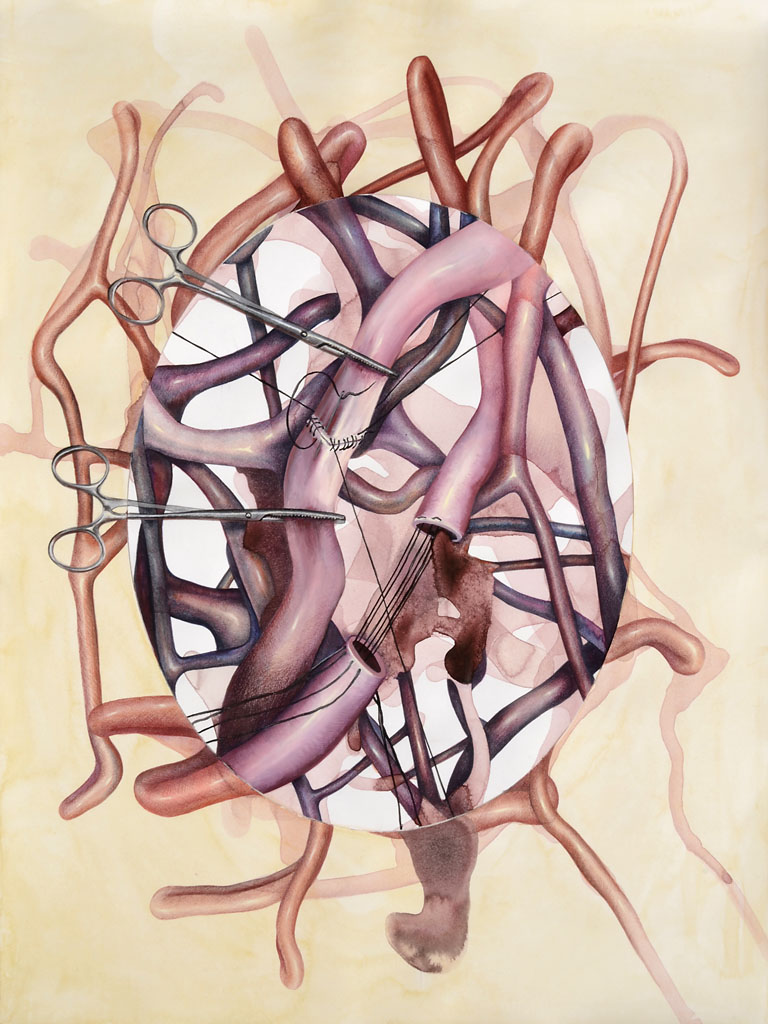

While working on several projects and experimenting with various media, somewhere along the way I developed an interest in medical illustration as a visual representation of the human body. I began reading philosophy texts on the human body and how we define it. I am very much interested in the fact that a medical illustration can never be an objective representation of the body. We all have subjective visceral experiences that differ from person to person, and these cannot be visually represented without something being lost in translation.

Ever since I became interested in this topic, I’ve been creating drawings and paintings that mix technical scientific images with things that are generally not meant to be there: abstract inkblots, random humorous intrusions and additions, sudden changes in rendering… The work tries to hint at things that medical illustration cannot represent—things that are very much embodied. Human experiences of pain, love, confusion, fear, happiness—all of these kinds of things reside in the body.

Photos of my work are available on my website but seeing those is not the same as seeing the work itself. Some of my drawings and paintings are several feet tall with unusual surfaces and textures that require movement while viewing. Regarding supporting my work, all of my paintings are for sale. If you are in the Chicago area and might be interested in purchasing a piece, you are welcome to come for a studio visit.